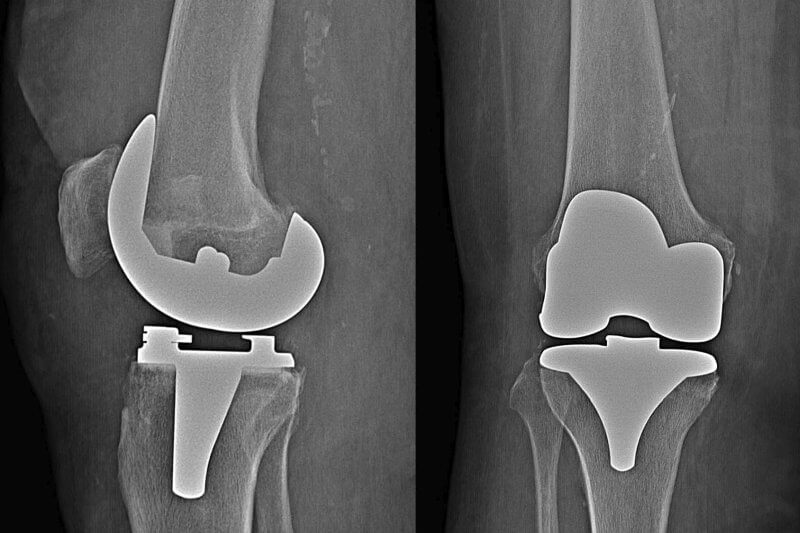

A knee prosthesis is an implant made from biocompatible materials that replace damaged joint tissues. Knee joint replacement is performed during a surgical procedure called arthroplasty. The implant is used to fill the gaps in the joint surface caused by tissue loss. Depending on the extent of cartilage damage, the replacement can be total or partial. The procedure aims to restore normal joint function and ensure adequate stabilization during movement. Unfortunately, a knee prosthesis is not permanent. It is estimated that a knee prosthesis should serve the patient for at least 15 to 20 years, but its actual longevity depends on several factors such as body weight, anatomical structure, and usage of the limb.

Types of Knee Joint Prostheses

Over 150 types of knee prostheses are currently available for surgical application. The type of implant chosen depends on the specific knee problem as well as the patient’s age, body weight, overall health, and activity level. The primary components of implants are made from metal alloys (cobalt/chromium) or metal-ceramic composites (oxidized zirconium) and durable plastic materials (polyethylene).

In total knee replacement, one of the most commonly used implants is the posterior-stabilized knee prosthesis. In this design, the cruciate ligaments are removed, and part of the implant replaces their function. Another frequently used implant is the cruciate-retaining knee prosthesis. It is important to note that selecting the appropriate type of prosthesis for a patient is an individual decision made by the doctor.

In most cases, the knee prosthesis used includes a tibial insert fixed in place. This means that the polyethylene tibial component is attached to the metal implant, and the femoral component slides over this smooth surface. For prostheses with a mobile insert, the polyethylene insert can move slightly within the metal tibial component. This design aims to provide patients with greater joint mobility.

Knee arthroplasty is divided into two types: total knee replacement, where the entire joint is replaced with an artificial surface, and partial knee replacement, where only one damaged component of the knee is replaced. In total knee replacement, which is more common of the two procedures, damaged bone and joint cartilage are removed and replaced with artificial implants tailored to individual needs to ensure maximum compatibility.

The procedure begins with the orthopedic surgeon making an incision in the knee and moving the kneecap aside to access the joint. The two menisci and the anterior cruciate ligament (ACL) are then removed. Depending on the type of prosthesis, the posterior cruciate ligament (PCL) may be retained or removed. During the main phase of the operation, the proximal tibia, distal femur, and cartilage—often accompanied by small bone spurs characteristic of osteoarthritis—are removed. The femur and tibia are then covered with metal implants to recreate the joint surfaces. If the patella has also deteriorated, its surface can be replaced with a polyethylene implant, though this is rarely done. The procedure concludes with layer-by-layer suturing of the wound. Total knee replacement surgery generally takes about 90 to 120 minutes, and most patients stay in the hospital for approximately a week.